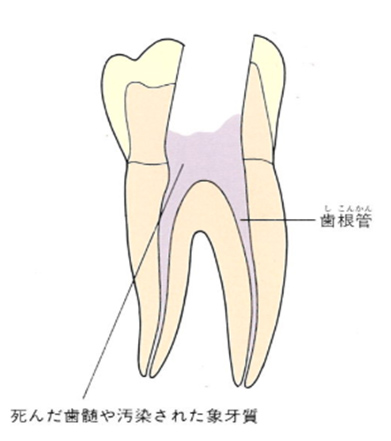

これまで説明してきたように、歯の中には歯髄(シズイ)組織が入っています。いわゆる神経のことです。この神経に虫歯などで細菌感染を起こし、歯根尖まで炎症が波及した状態が、根尖性歯周炎(コンセンセイシシュウエン)です。

根尖性歯周炎に罹患した後、身体の防御反応で生じるのが歯根のう胞です。歯根のう胞は根管内の細菌が骨組織の中に侵入してくるのを防ごうとする結果あのような球形になります。

上の図にあるように神経の管に入れる薬が根尖(コンセン)まで入っていなかったり、途中までしか入っていなかったり、薬がスカスカだったりするとその空間にばい菌が繁殖して感染を起こします。

そうすると神経を取ったはずなのに、その後歯ぐきが腫れて痛くなるのです。

この根っこの病気を根尖性歯周炎というのです。そしてこの根尖性歯周炎を治すことを感染根管治療と言います。